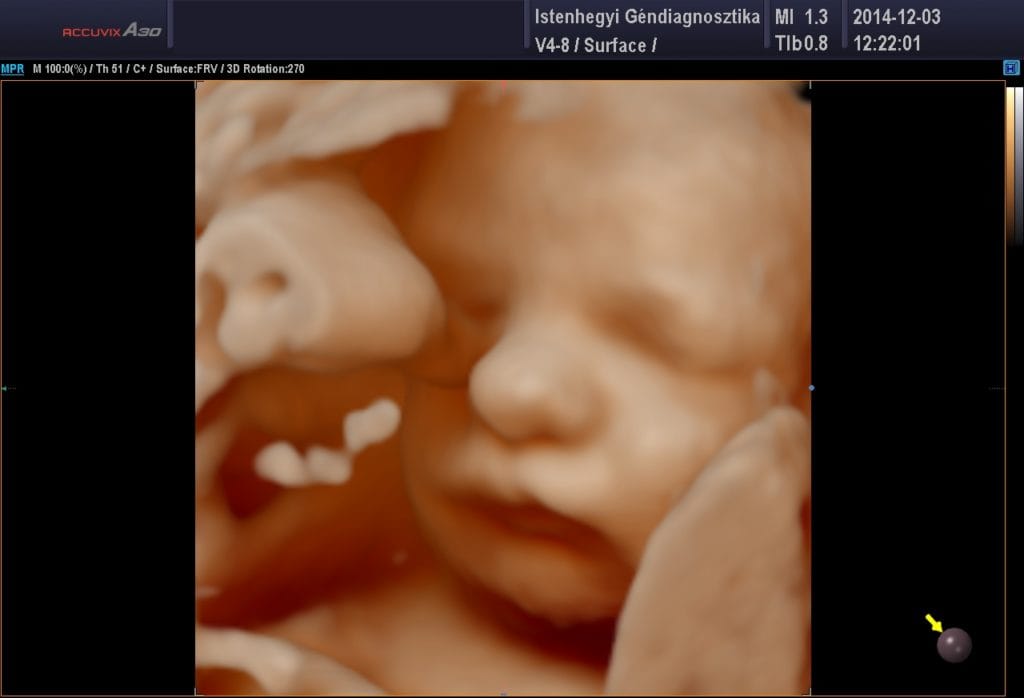

Legújabb ultrahang berendezésünk képes FRV (Feto Realistic View – fotorealisztikus magzati kép) minőségben, élethű árnyékolásokkal képes megjeleníteni az ultrahangos képet, amely páratlan látványt nyújtva enged betekintést a méhen belül fejlődő magzat életébe, ha a baba elhelyezkedése lehetővé teszi.

A Babamozi mindig terhességi ultrahangvizsgálattal indul. Ennek során a magzat elhelyezkedését, a méhlepény állapotát, a magzatvíz mennyiségét, illetve a magzati szervek fejlődési ütemét és működését vizsgáljuk elsősorban két dimenzióban. Ezt követően indul a „mozizás”, mikor az ultrahanggal négydimenziós síkra váltva megtekinthetjük a baba mozgását, testhelyzetét és akár az arckifejezését is!